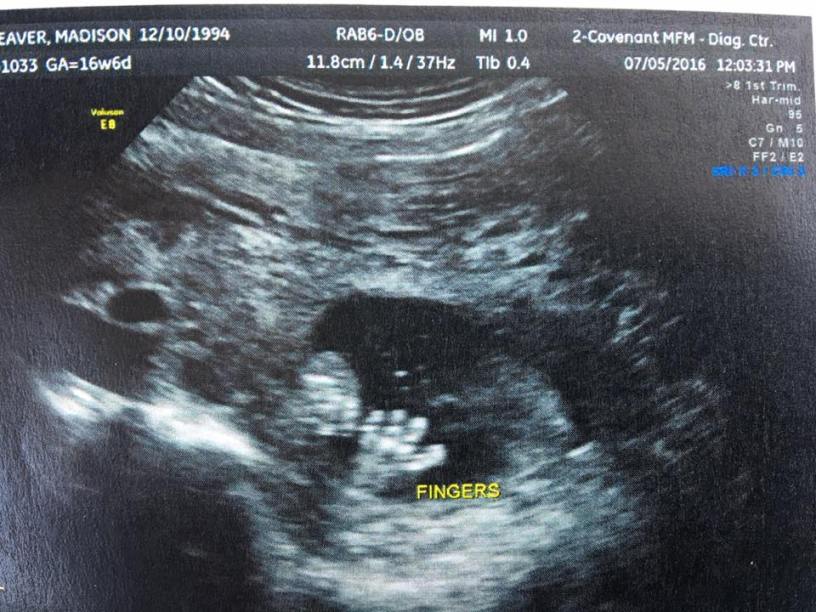

I would have been 20 weeks pregnant yesterday. Some people may not know how significant this week is, but moms do. I would be half way through the pregnancy. I would feel the movements of my little one from inside. We would know the gender and the name.

Moms of loss don’t have pictures of their precious one giggling or videos of them crawling. We don’t have measurements to share with you or a time of birth. We don’t have a baby for you to hold and to kiss, but we have one waiting for us upstairs. Our angel matters to us, and it means the world to know they matter to you too.